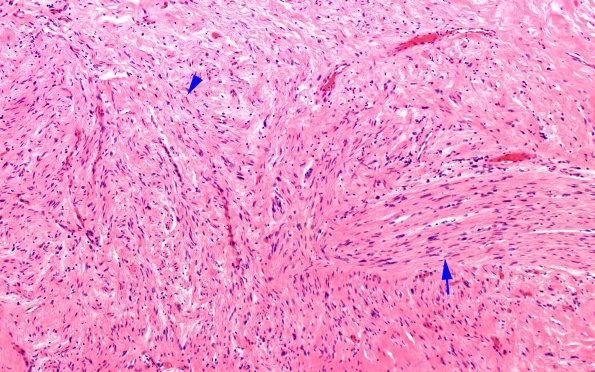

Washington University Experience | PERIPHERAL NEUROPATHY | 19 TRAUMATIC INJURIES | 13B2 Neuroma, traumatic (Case 13) H&E stump prox 10X 2 copy

Higher magnification of the composition of the mass shows tangles of disorganized neurites (arrow) and residual fascicles (arrowhead)